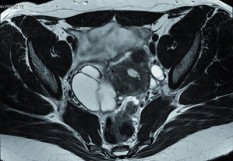

Endométriose, grossesse, maladies cardiovasculaires... Dossier spécial santé des femmes

À l’occasion de la Journée internationale des droits des femmes, le 8 mars, ce dossier aborde les nouveautés concernant les pathologies féminines, ainsi que les inégalités entre hommes et femmes sur le plan médical.

Gynécologie-Obstétrique Cancer du sein Cardio-vasculaire HTA